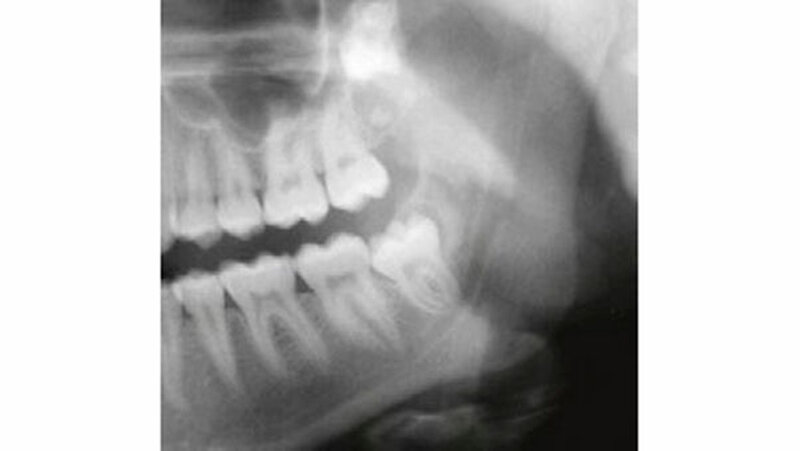

Auf dem mitgelieferten vier Jahre zuvor erstellten Orthopantomogramm (OPT) waren noch keine Hinweise auf das Vorhandensein einer Veränderung regio 32-34 sichtbar (Abbildung 2). Ein Jahr später konnte anhand des OPT bereits eine radioopake Struktur regio 33, 34 festgestellt werden (Abbildung 3). Auf dem aktuellen OPT und digitalen Volumentomogramm (DVT) zeigten sich regio 32-34 lingual multiple, rundliche, unterschiedlich große Radioopazitäten, umgeben von einer radioluzenten Zone.

Die Ränder der radioluzenten Zone waren sehr gut zum umgebenden Alveolarknochen abgrenzbar (Abbildung 4, 5). Eine dreidimensionale Diagnostik (DVT) macht aus dreierlei Gründen Sinn: 1. Erleichterung der Patientenaufklärung, 2. optimale Lagebestimmung des Tumors in Bezug zu benachbarten anatomischen Strukturen wie Nachbarzähne und Nerven, 3. präoperative Bestimmung der Anzahl zahnähnlicher Strukturen (zusammengesetztes Odontom), um kontrollieren zu können, ob während des operativen Eingriffs alle hartgewebigen Tumoranteile entfernt worden sind.